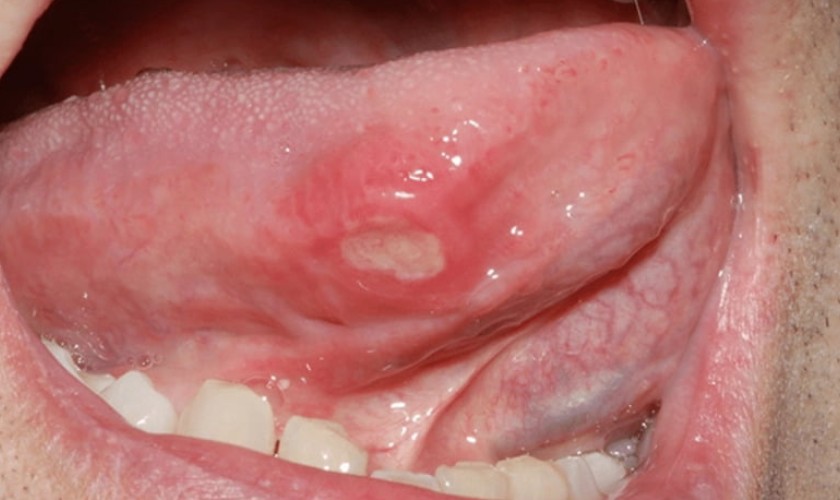

Nhận biết nhiệt lưỡi qua hình ảnh

Để dễ dàng nhận biết nhiệt lưỡi và có cách điều trị sớm, bạn có thể tham khảo một số hình ảnh nhiệt lưỡi dưới đây.

Vết loét xuất hiện bên dưới lưỡi

Nhiệt lưỡi là tình trạng niêm mạc lưỡi xuất hiện các vết loét hình tròn hoặc hình oval có màu trắng sữa với viền đỏ xung quanh. Những vết loét này có thể xuất hiện đơn lẻ hoặc thành từng đám, gây đau rát, ảnh hưởng nhiều đến việc ăn uống. Trong hầu hết trường hợp, nhiệt lưỡi sẽ tự khỏi sau 7 - 10.

Bên cạnh triệu chứng đau rát, nhiệt lưỡi còn gây ra các triệu chứng như khô miệng, khát nước liên tục, tê lưỡi, ngứa lưỡi, vị giác kém,... Khi vết loét hết sưng và kích thước được thu nhỏ lại, các triệu chứng này sẽ giảm dần.